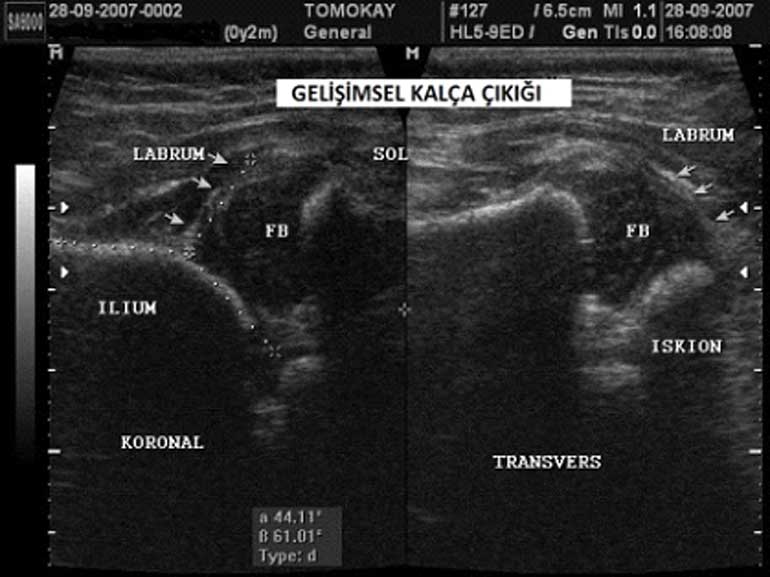

نعم، بفضل خبرائنا المتمرسين في مجال التصوير الطبي للأطفال وبروتوكولات التصوير الآمنة التي نتبعها، نقدم خدمات متخصصة للرضع والأطفال. s.leo